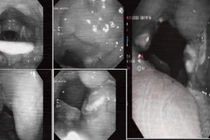

Tại Khoa Hồi sức tích cực Nhi, Bệnh viện Quốc tế Sản Nhi Hải Phòng, các bác sĩ đang điều trị tích cực cho 3 bệnh nhi tay chân miệng biến chứng viêm não. Các trường hợp nhập viện đều trong tình trạng nặng, cần theo dõi sát và can thiệp chuyên sâu.

Phòng khám Đa khoa Medlatec Tây Hồ vừa điều trị cho một bệnh nhân bị viêm amidan cấp mủ. Đây là một trong những biến chứng nguy hiểm của viêm amidan cấp tính, có thể tiến triển nhanh, gây nhiều hệ lụy nếu chậm trễ điều trị.

Chị N.N.H. (24 tuổi, Hà Nội) đến Phòng khám Đa khoa Medlatec Tây Hồ với lý do đau họng, nuốt vướng. Trước đó 5 ngày, chị H. có tình trạng sốt liên tục, có sử dụng thuốc hạ sốt sau đó lại sốt lại, kèm theo nuốt vướng, không ho, không ngạt mũi chảy nước mũi.